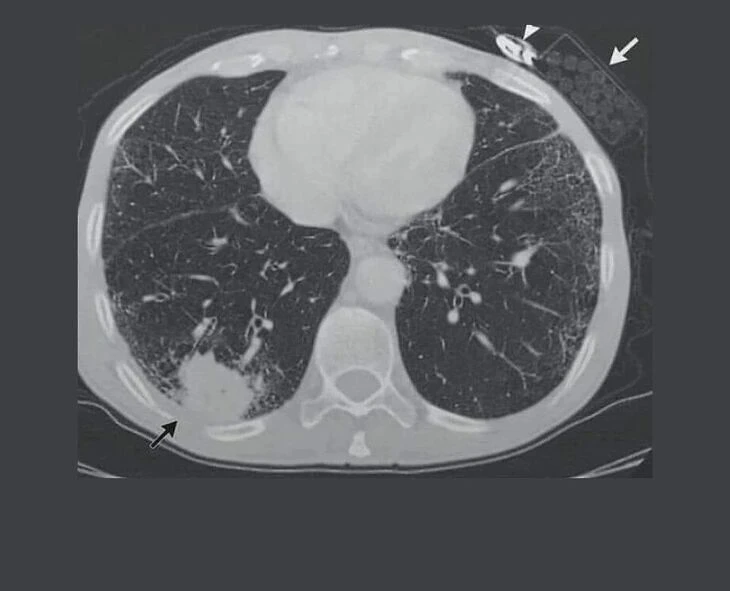

நுரையீரல் புற்றுநோயால் பாதிக்கப்பட்ட ஒருவர், அதற்காக எடுத்த ஸ்கேனிங் ரிப்போர்ட் ஒன்று இணையத்தில் வைரலாகி உள்ளது. முதலில் பார்த்தால் சாதாரணமான படமாக இருக்கலாம். படத்தில் பிளாக் அம்பு இருப்பது தான் புற்றுநோய். சரி, இதில் வைரலாக என்ன இருக்கு’னு கேக்குறீங்களா? வலது பக்கம் டாப்’ல பாருங்க. ஸ்கேன் எடுக்கச் சென்றவர் பாக்கெட்டில் சிகரெட், லைட்டரை அப்படியே வைத்துள்ளார். யாரு சாமி நீ….